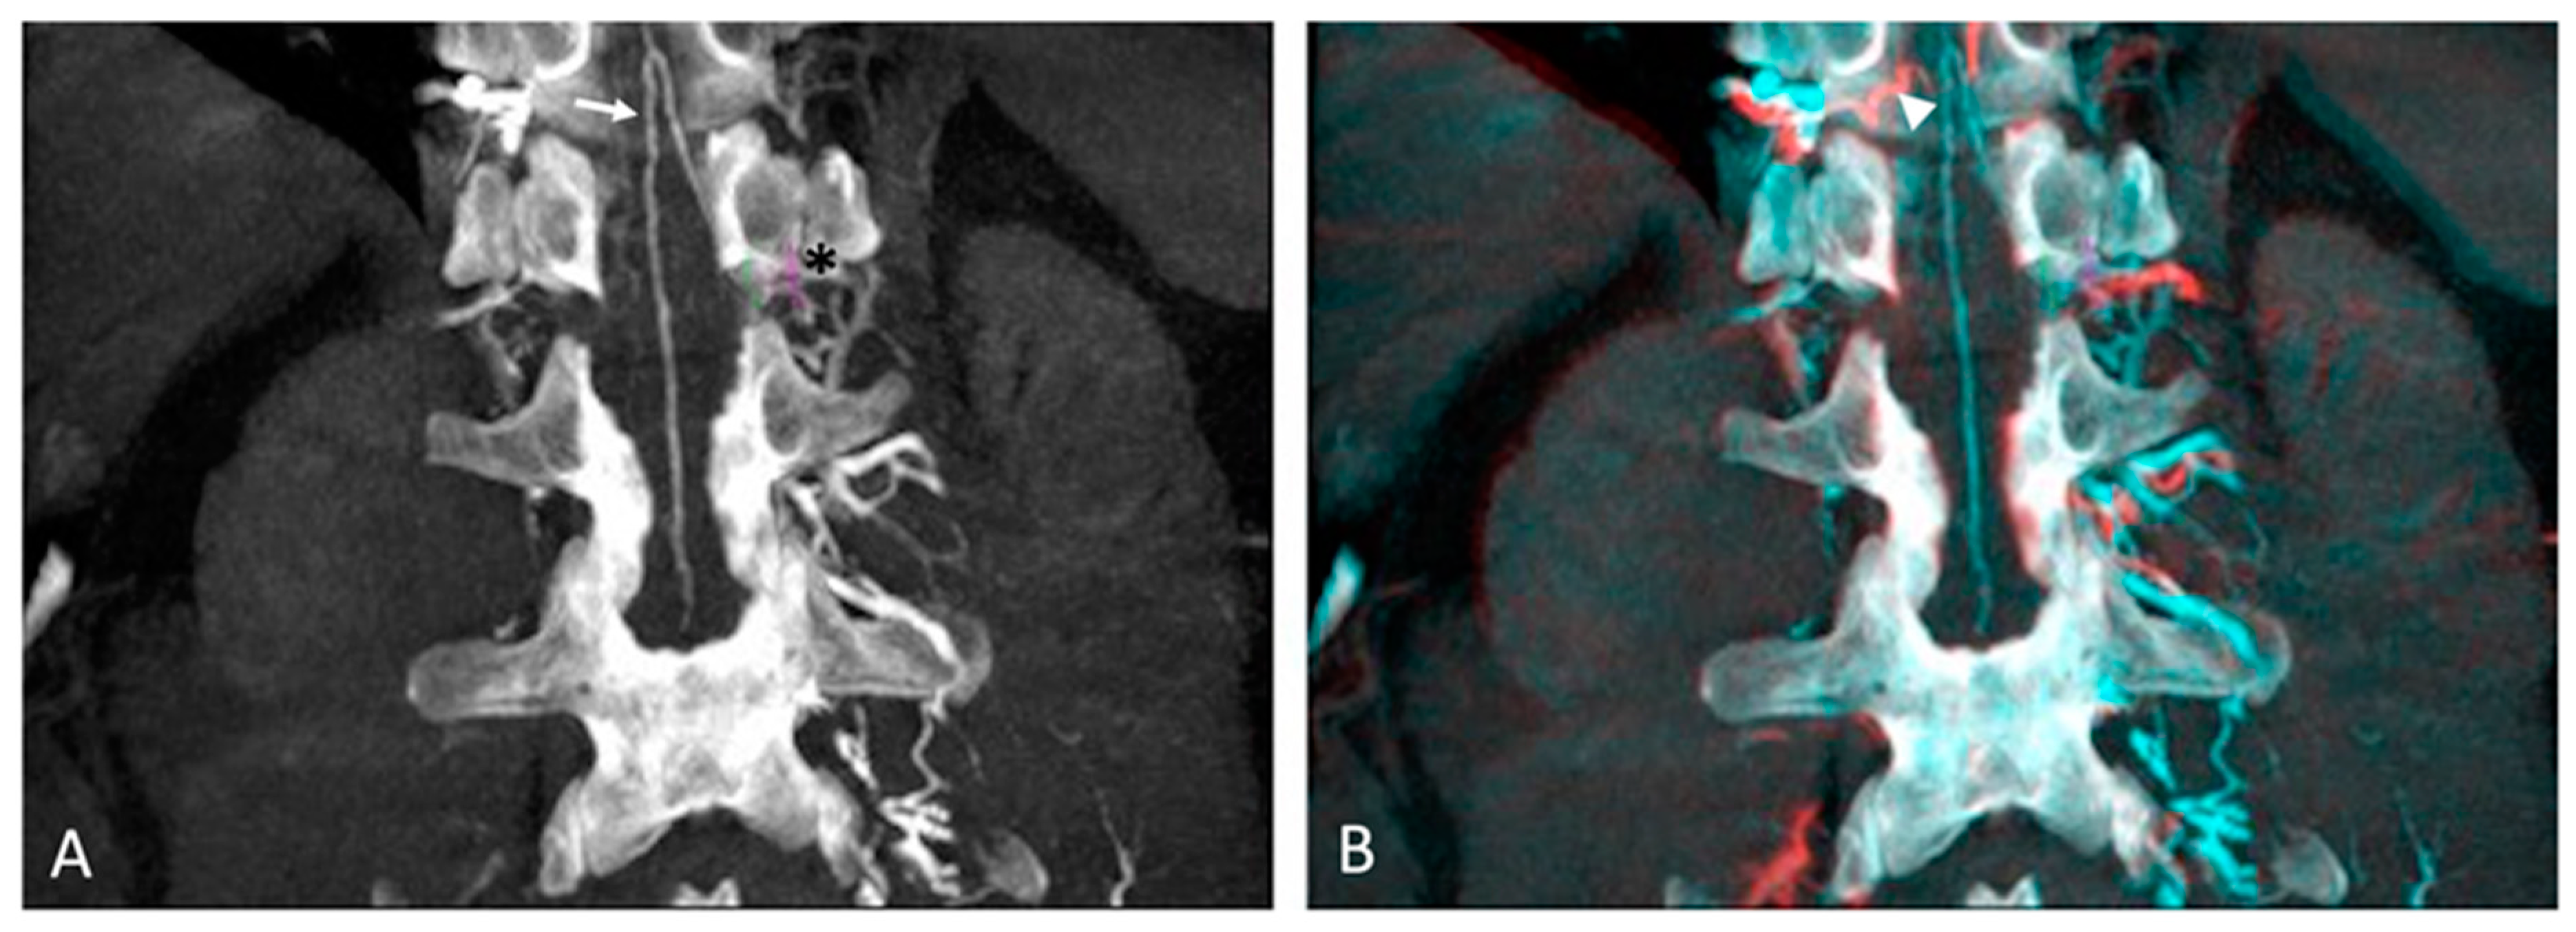

2.2. Procedure and CBCT Data Acquisition

2.3. Post-Processing and Image Analysis